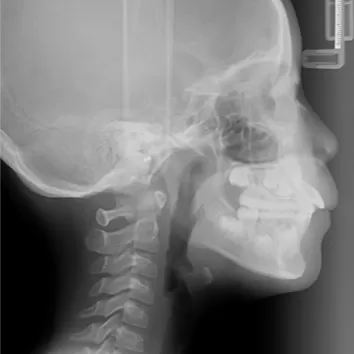

Rayons X avant le traitement

[Radiographie panoramique/Céphalogramme latéral]